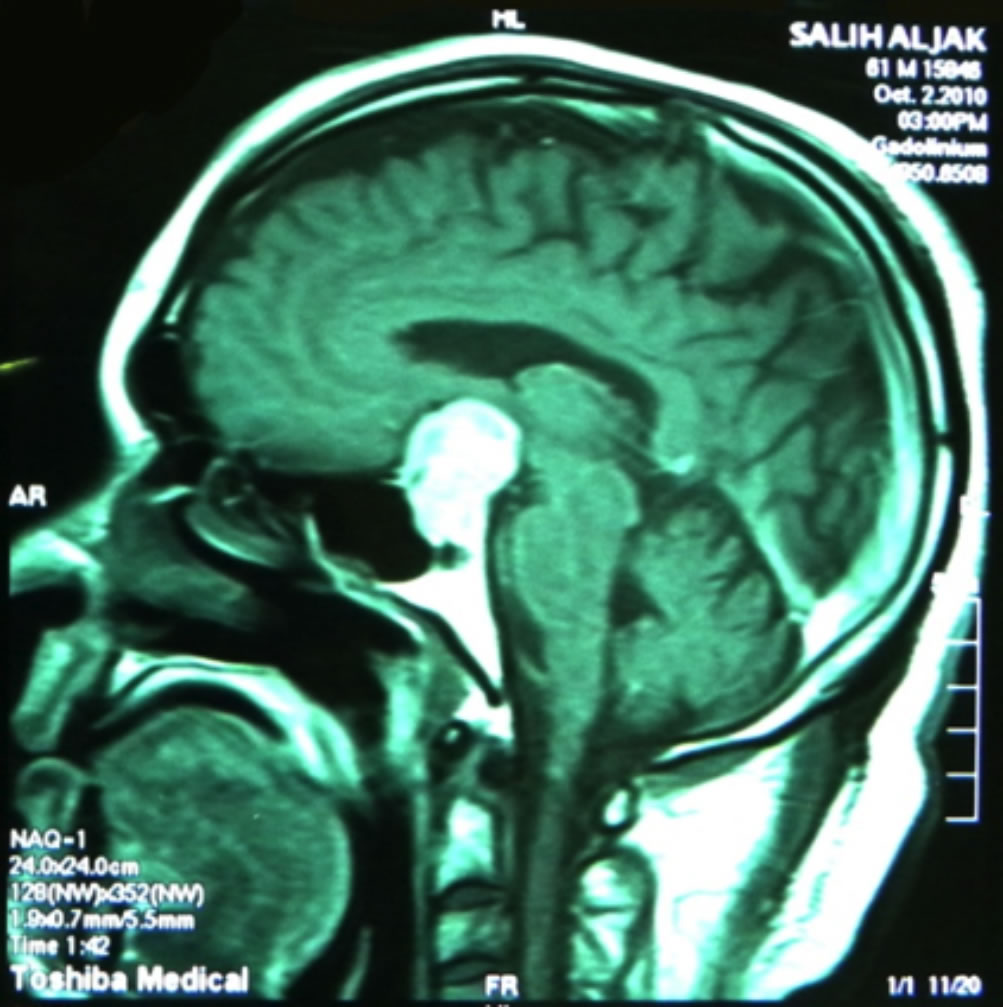

Bitemporal hemianopic defect due to chiasmal lesions. These can easily be confused with glaucoma, especially if the two pathologies coexist in the same patient (glaucoma plus pituitary tumour) (Figure 13).

Figure 13a. These are the right and left visual fields of a 61 year-old patient, who was diagnosed with POAG 15 years prior to presentation. Both optic discs were terminally cupped. The IOP was poorly controlled in both eyes; however, the patient was aware that his right eye was worse than the left eye.  Looking at the VF of the left eye, there is a clear temporal field defect respecting the vertical midline.

Figure 13b. An MRI revealed a large pituitary adenoma responsible for visual loss in both eyes (on top of his POAG).